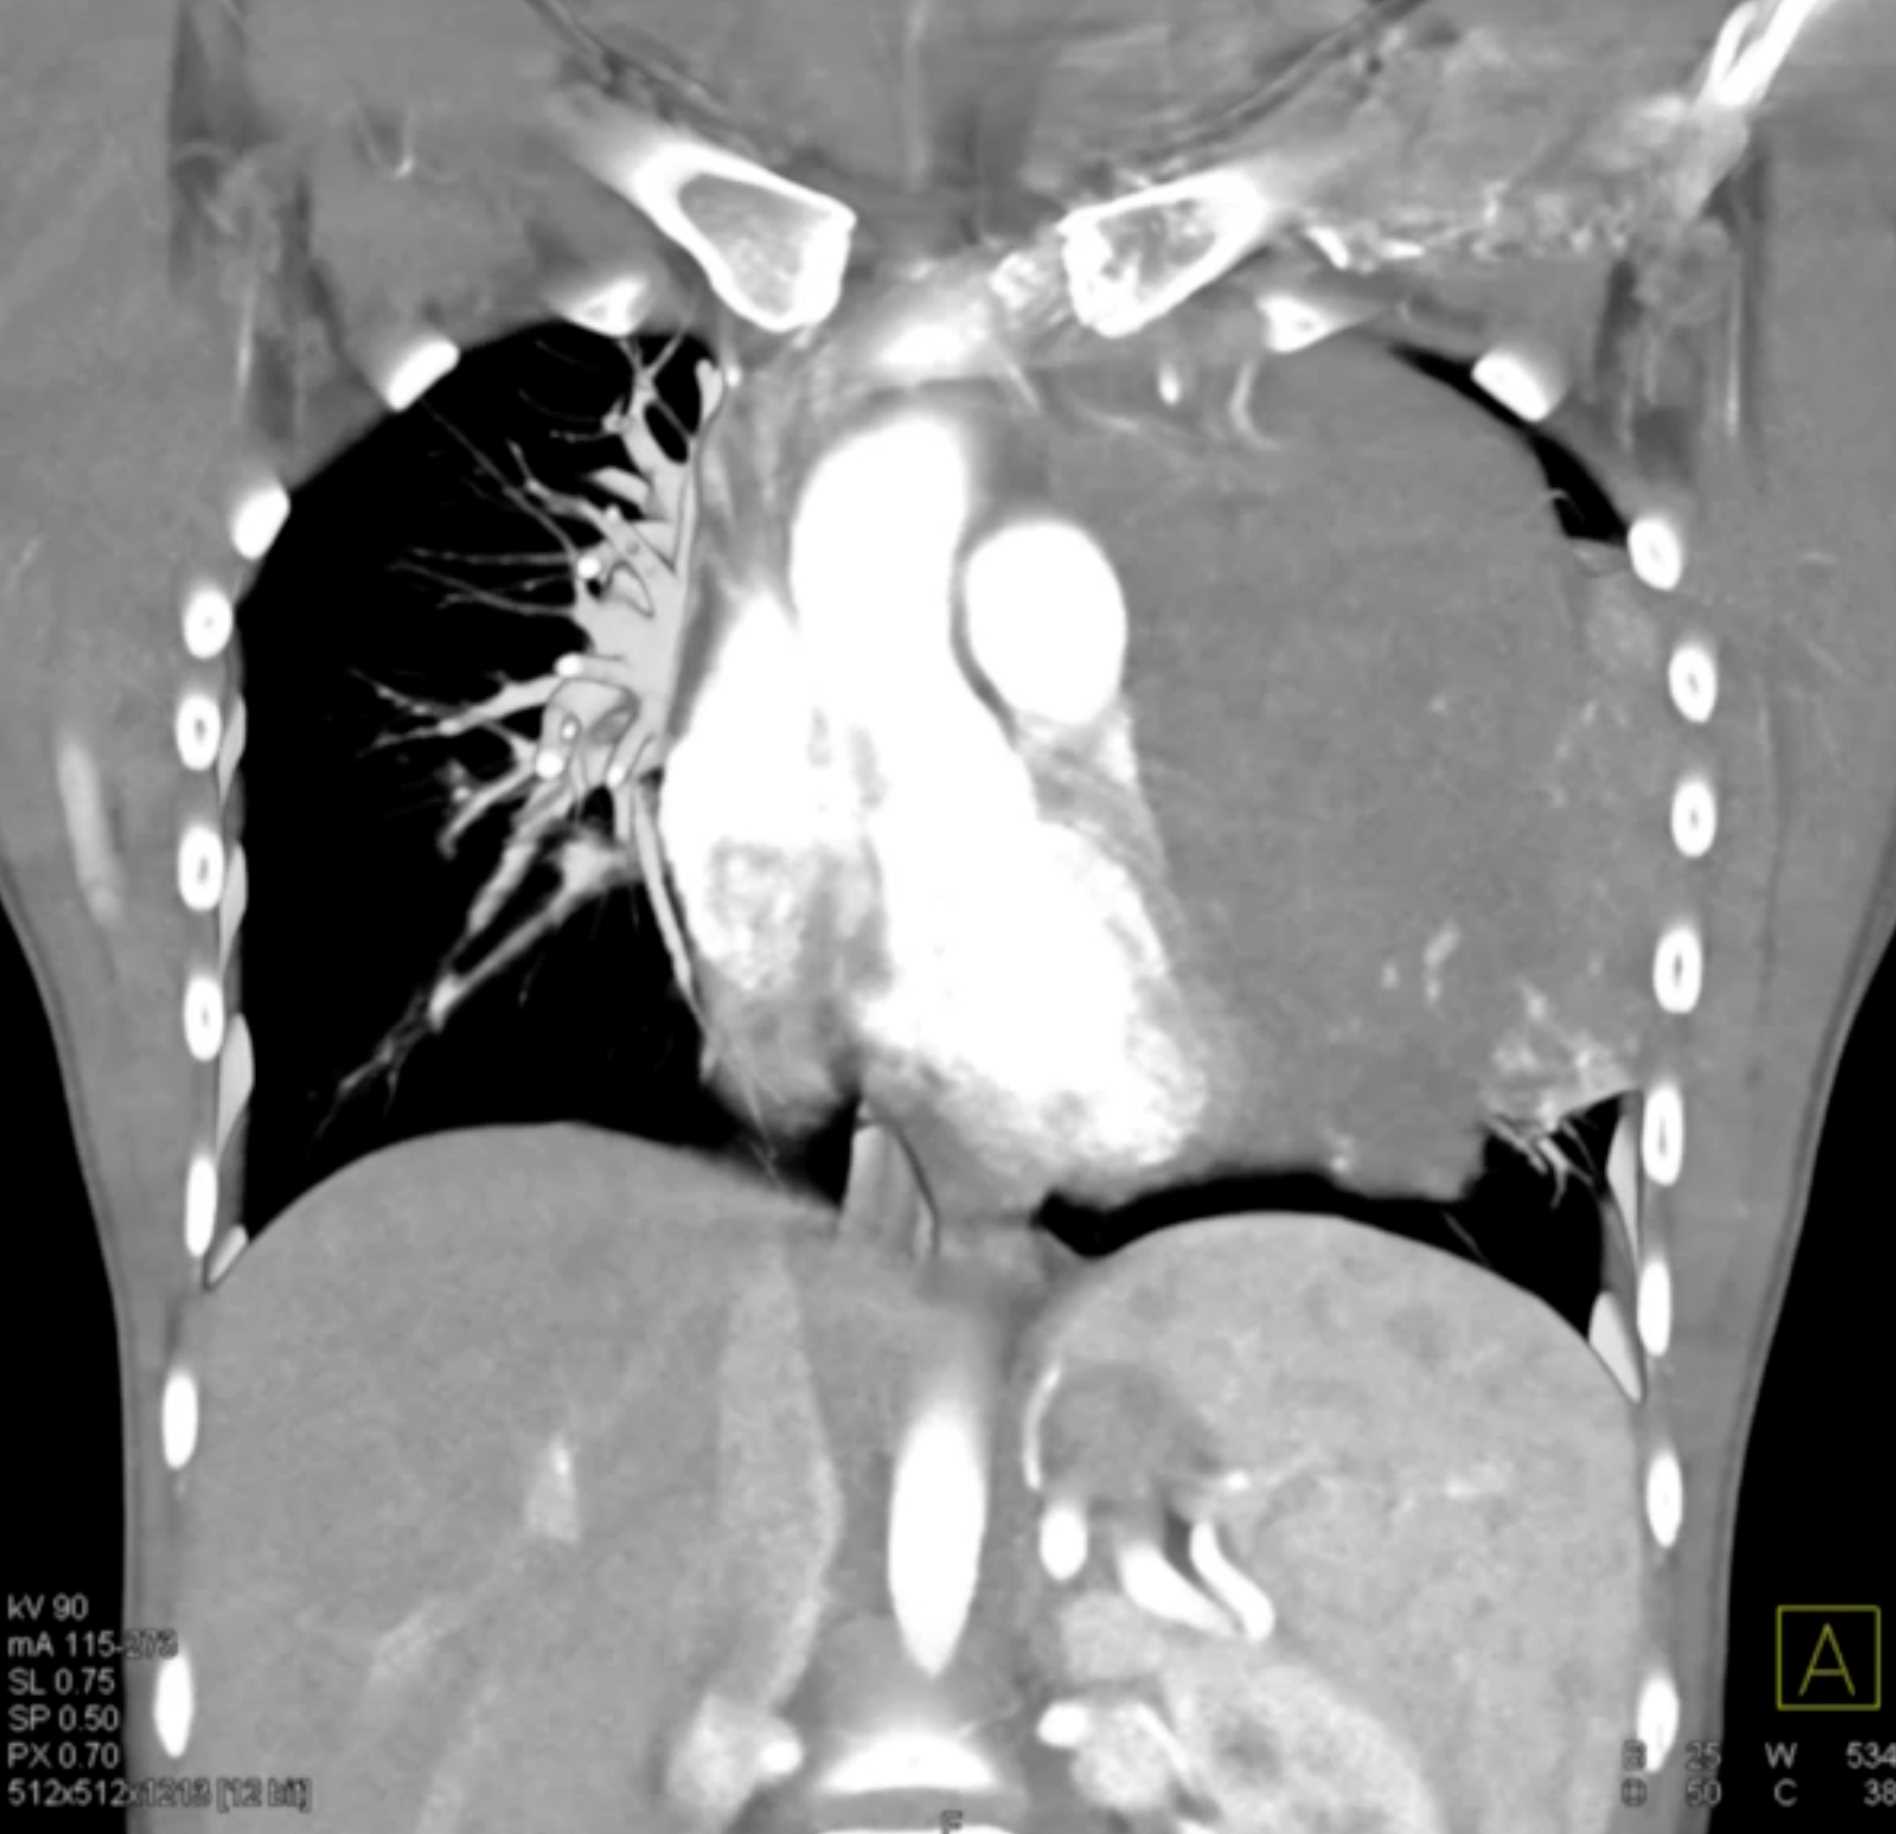

Subtle Adenocarcinoma Pancreas